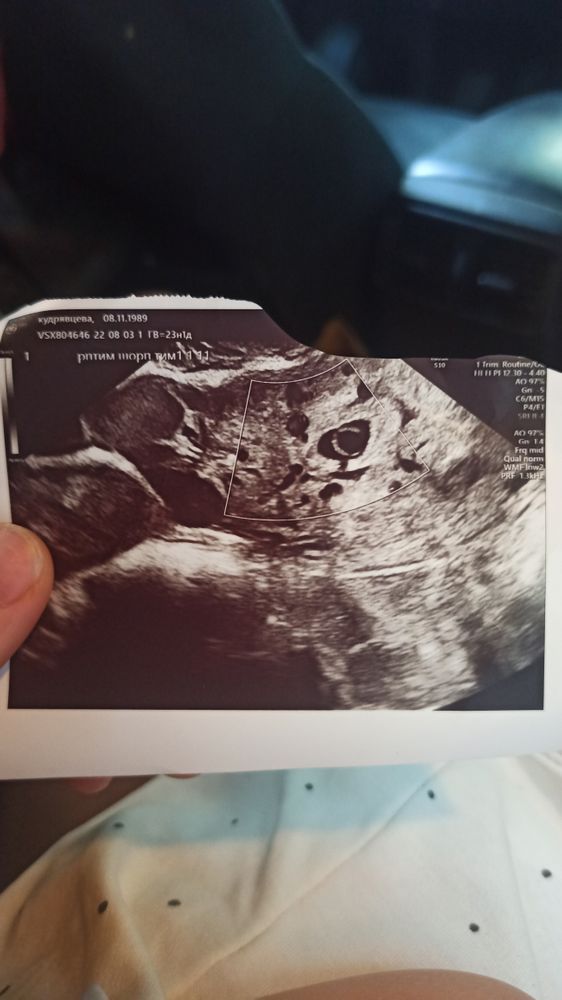

Плодное яйцо 21 мм без эмбриона

Первое УЗИ, ПЯ 21-27 мм, эмбриона нет, жёлтого мешочка вроде тоже. Гинеколог сказала, всё нормально, но обязательно приходи через 15 дней.

Марина, ну да, в протоколе 21-27 мм, беременность раннего срока. Может забыли запятую поставить, но её там точно нет. А на мониторе пя выглядело супер маленьким

Марина, спасибо вам большое за внимание! Вот мои протокол и фото. Очень большая разница в размерах на вашем снимке и моем. Может правда описание неточное? Ну мне хоть легче ждать будет 2 недели.

Да у вас точно не 21 мм,это ошибка в протоколе,все хорошо у вас и соответствует вашему сроку,зря только панику мы тут навели, естественно в таком пя ни жм ни эмбриона не будет,это совсем маленький срок